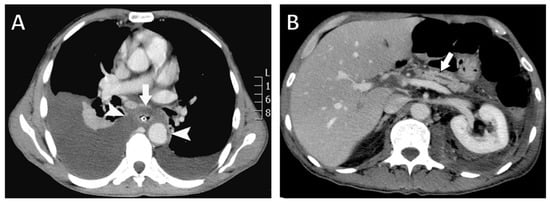

Figure 2.

Contrast-enhanced computed tomography (CT) findings. (A) Axial CT image showing a fluid collection surrounding the esophagus (arrow) extending through the mediastinum and communicating with both pleural cavities (arrowheads). A nasogastric tube is visualized within the esophageal lumen. (B) Axial CT image demonstrating pancreatic atrophy with dilatation of the main pancreatic duct (arrow).